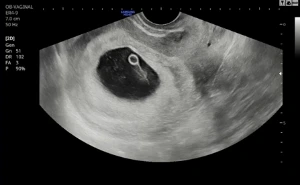

귀여운 타원형의 아기집을 보고 진료실을 나오는데, 접수처의 간호사가 물었다. "낳으실 거예요?"